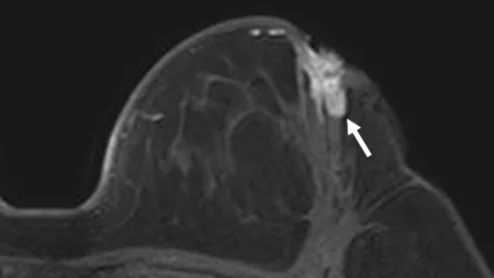

Experts believe the tool could better inform surveillance strategies in women who have been treated for breast cancer.

breast radiologist breast cancer mammography